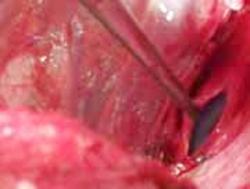

Pneumotorace deschis Pneumotorace

deschis Traumatism

toracic deschis cu

hernierea parenchimului pulmonar

(stanga) Contuzie pulmonara (dreapta)